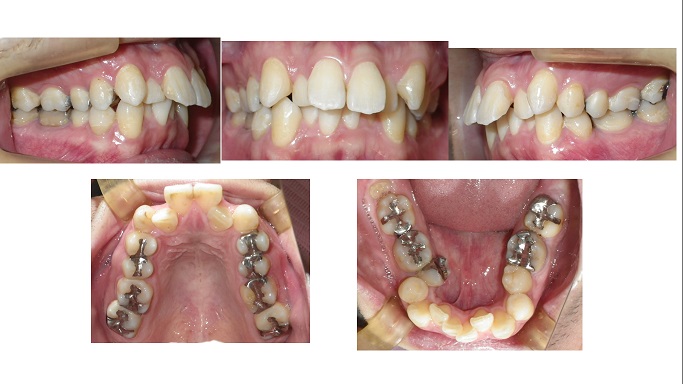

矯正症例63 AngleclassⅠ上顎前突 叢生,能代市,北秋田市,大館市

治療開始年齢16歳、抜歯部位:上顎左右4番、下顎左右5番、上顎左右7番。治療期間2年2か月。来院回数:33回 使用装置:マルチブラケット法による歯列矯正、歯列矯正用アンカースクリュー併用高校1年生の2...